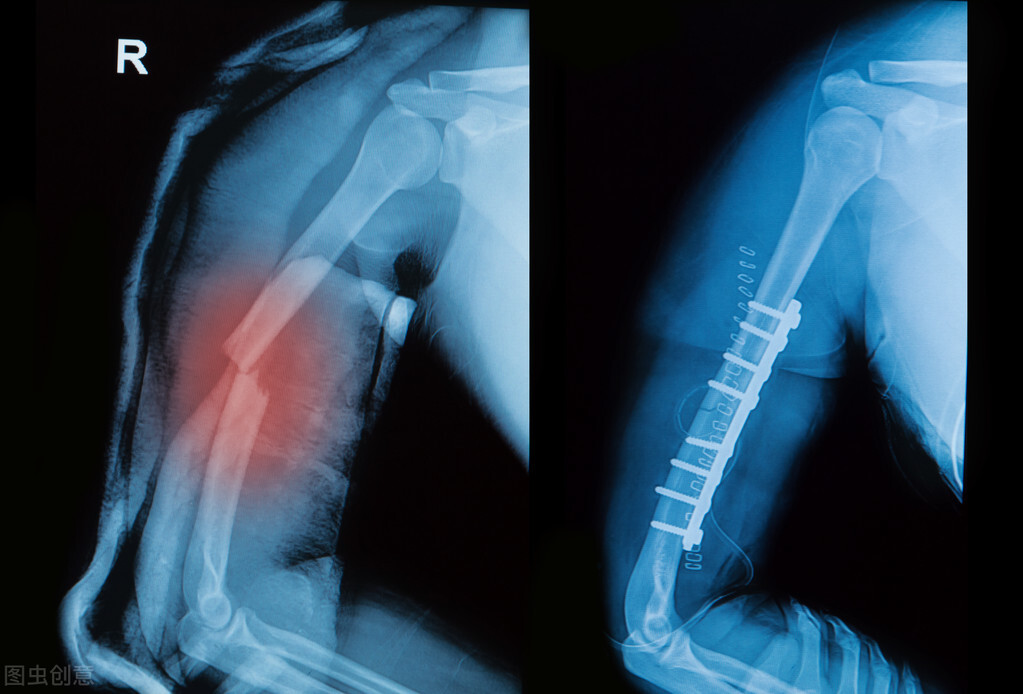

4月27日,上海一家医院收治了一名特殊的急诊患者。该患者为女性,在公司团建活动中掰手腕导致受伤,上臂肱骨被扭开花,经诊断为右臂上端粉碎性骨折,目前接受了钢板内固定手术。

骨折的治疗原则是:复位、固定、功能锻炼。